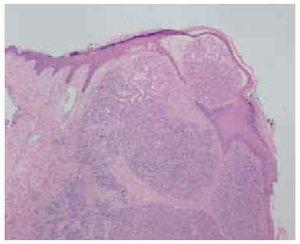

Fig. 3.--Imagen histopatológica a pequeño aumento, donde no se observa la presencia de vaso nutricio en la profundidad de la lesión. (Hematoxilina-eosina, x40)

Un niño de 15 años de edad, con el único antecedente de exéresis un año antes de un histiocitoma fibroso benigno localizado en la ceja derecha, consultó por una lesión tumoral exofítica de 5 mm de diámetro, de color rojizo, superficie lisa y friable al tacto, localizada en la zona clavicular izquierda. La lesión había aparecido un mes antes y había crecido de manera progresiva. Se realizó curetaje y electrocoagulación de la lesión. El estudio histológico de la pieza mostró una proliferación lobular de capilares que confirmó el diagnóstico de granuloma piogénico. A los 5 meses notó la aparición de cuatro nuevas lesiones de hasta 7 mm de diámetro, clínicamente similares a la tumoración previa, agrupadas en un área de 3 cm alrededor de la lesión extirpada anteriormente (fig. 1). Se realizó de nuevo curetaje y electrocoagulación de las lesiones sin recidiva en los 2 años posteriores. El estudio anatomopatológico fue idéntico al previo (fig. 2), sin observarse vaso nutricio en la profundidad de la lesión (fig. 3).

Microscópicamente se observan cúmulos bien delimitados de capilares proliferantes de patrón lobular dentro de una estroma edematosa relativamente rica en mucina1. En la parte superficial puede observarse edema, dilataciones capilares, inflamación y tejido de granulación. En algunos de los casos recidivantes se ha descrito la presencia de un vaso nutricio en la profundidad de la lesión que podría explicar la tendencia a la recurrencia16. Además, en la parte central del nódulo se han descrito áreas de proliferación vascular en forma de anastomosis de vasos dilatados y un incremento de células endoteliales, que semejan un angioendotelioma16. Estos hallazgos no se observaron en nuestro paciente.